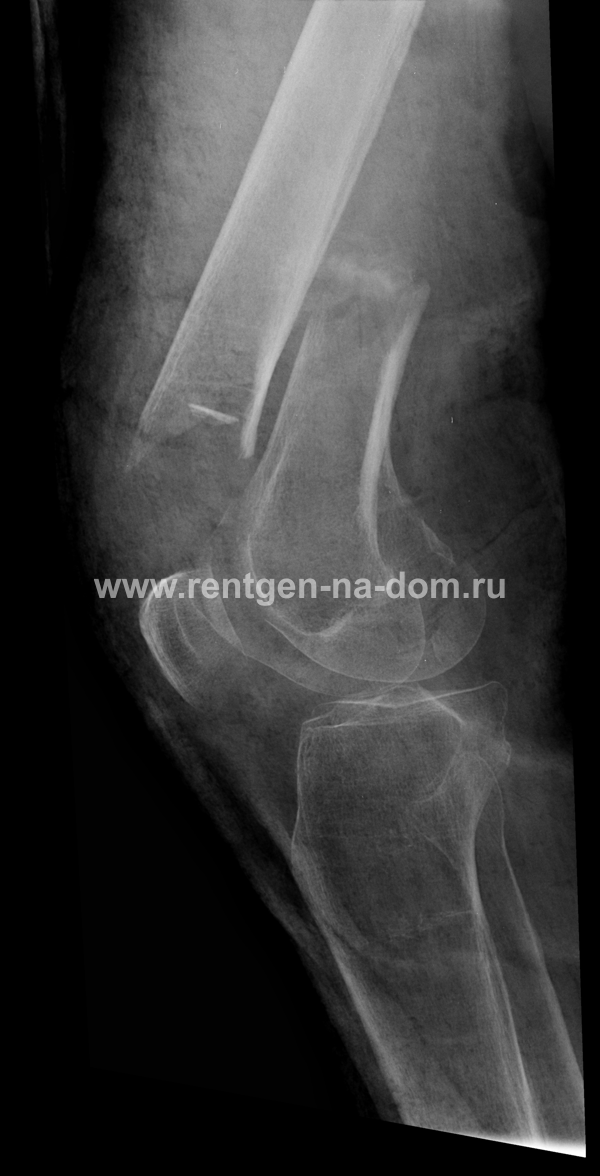

Решающее значение в установлении диагноза перелома шейки бедра имеет рентгенография тазобедренного сустава. У пожилых пациентов приведенные выше симптомы могут проявляться нечетко, а такие заболевания как инсульт или невропатия, вообще, не позволят поставить правильный диагноз без рентгена. Где сделать рентген? Перелом шейки бедра всегда сопровождается сильной болью, поэтому любые лишние движения оборачиваются новыми мучениями, а сопутствующие заболевания внутренних органов усугубляют ситуацию! Решение есть - воспользоваться уникальной услугой – цифровой рентген на дому. К вам приедет врач рентгенолог-травматолог, который выполнит весь комплекс лечебно-диагностических мероприятий и подробно расскажет, что делать дальше.

Получение качественных рентгеновских снимков на дому предъявляет серьёзные требования к рентгеновской аппаратуре. Далеко не каждый переносной рентгенаппарат позволяет получать снимки необходимого качества, чтобы достоверно поставить диагноз. Используемый нами рентгенаппарат АРА 110/160 в комплексе с компьютерным радиографом позволяет получать цифровые рентгеновские снимки высокого качества у пациентов различной комплекции и является уникальной услугой в Санкт-Петербурге, предоставляемой на дому.